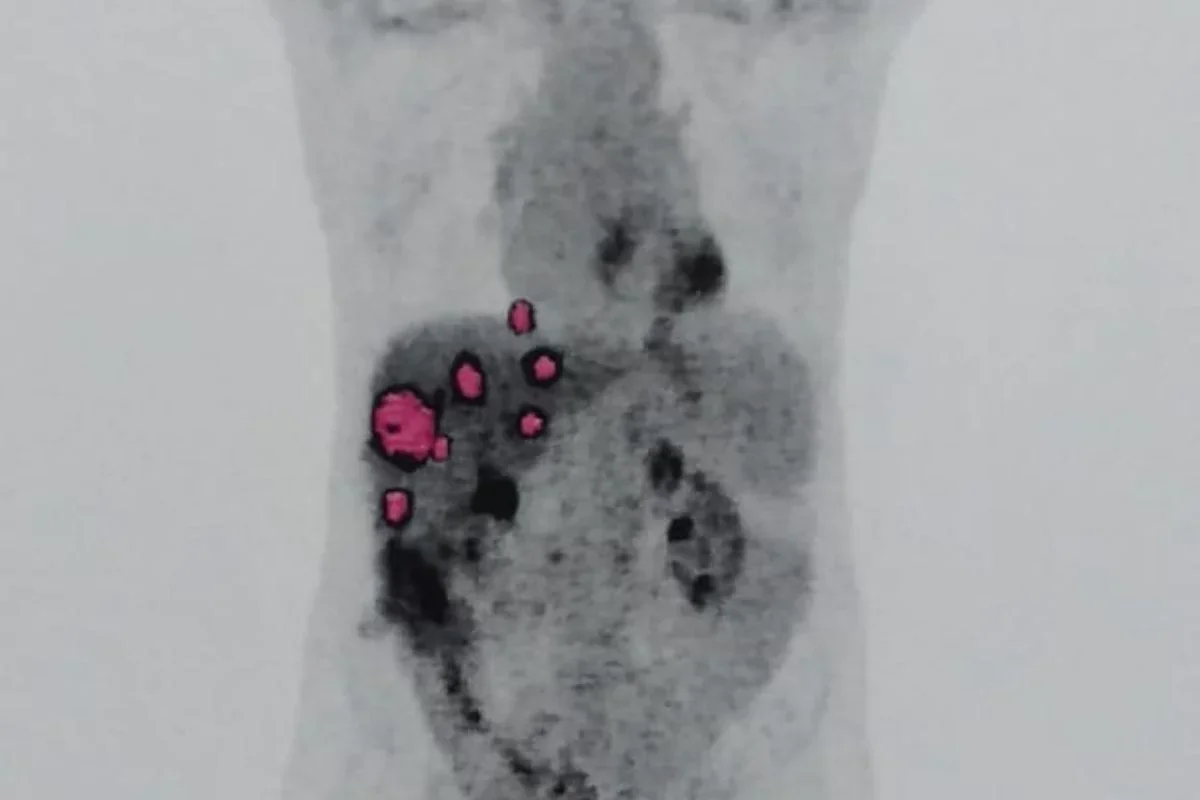

Geraldo Vaz Junior, de 58 anos, passou por um transplante de fígado em março de 2023, acreditando que seria o início de uma nova fase após enfrentar a hepatite C. No entanto, meses depois, exames revelaram que o órgão transplantado continha um adenocarcinoma, um tipo de tumor maligno. Pouco tempo depois, ele foi diagnosticado com metástase pulmonar do mesmo câncer.

Especialistas afirmam que a transmissão de câncer em transplantes é extremamente rara, com incidência inferior a 0,03%, mas que o risco existe. O oncologista Paulo Hoff explicou que, apesar da triagem, tumores ocultos podem passar despercebidos. Segundo ele, o câncer veio do fígado transplantado, indicando que a doadora teve a doença em algum momento.